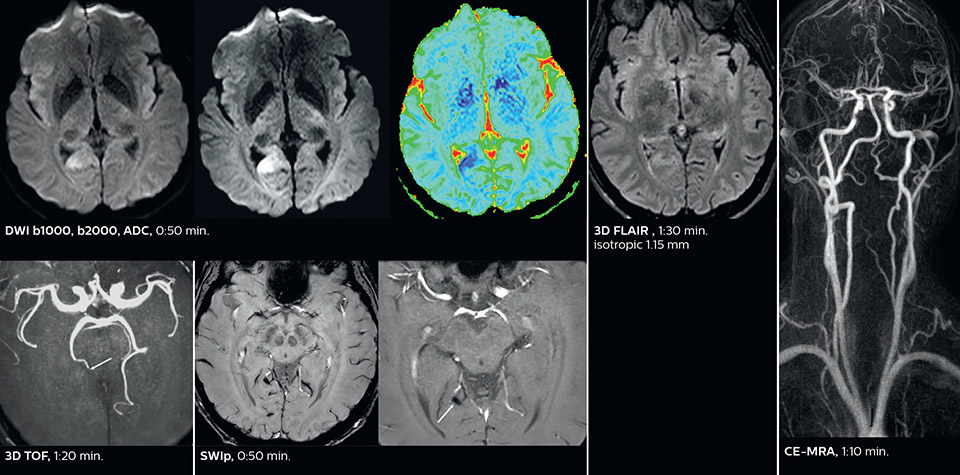

Comprehensive stroke MRI within acceptable time

Dr. Savatovsky appreciates the improvements and flexibility that Elition with Compressed SENSE and MultiBand SENSE provides, particularly for stroke patients. “For stroke, it allows us to cut about 5 minutes off of our stroke protocol, or to keep the same acquisition time and get more insights.”

The ability to perform more sequences can help in making a swift and confident diagnosis. “For example, our stroke cases usually include the regular sequences that every center does (b1000 diffusion, FLAIR, time-of-flight angiography), but we also image supra aortic vessels, and we can replace a gradient echo sequence with a fast 50-second susceptibility-weighted sequence, and all of this doesn’t add much time. because all the regular sequences are accelerated on Elition.”

“The time savings with Compressed SENSE and MultiBand SENSE make it easier to add sequences to give us additional insights. Depending on the context and the first results, we might add a DSC perfusion to assess the ischemic penumbra, an ASL perfusion to help find an alternative cause in case of normal diffusion, or add a high-resolution T1 sequence for a stroke patient, to quickly assess wall imaging in emergency cases. The additional sequences can help improve patient management, because we can already consider some alternative diagnoses if the morphological MRI is normal.”

Improved diffusion imaging in stroke patients

Using MultiBand SENSE allowed the staff to improve their diffusion quality. “Our diffusion sequence was already fast before, about 40 seconds. Now with Elition, it still lasts 40 seconds, but we improved the spatial resolution by 0.2 mm and use high b-values to be more sensitive to visualize changes related to acute stroke,” says Dr. Savatovsky.

“We now also developed a high resolution DTI sequence (1.3 x 1.3 x 2 mm) that can be reformatted and takes 2 to 5 minutes depending on the coverage. We use it every time we have a doubt, or when we expect the diffusion to be abnormal but don’t see that on the fast sequence. We occasionally spot small ischemic infarctions that would not have been visible with the regular diffusion sequence.”

Fast acute stroke protocol

This is an example of acute ischemic stroke with distal occlusion of the right posterior cerebral artery. Note the improved visibility of the ischemic territory on the diffusion weighted image with high b-value. The 3D FLAIR shows a distal PCA occlusion. The fast SWIp depicts the thrombus on the isolated second echo image. The total scan time (including SmartBrain, preparations and a fast 3D T1w TSE Gd) is 8:00 minutes.